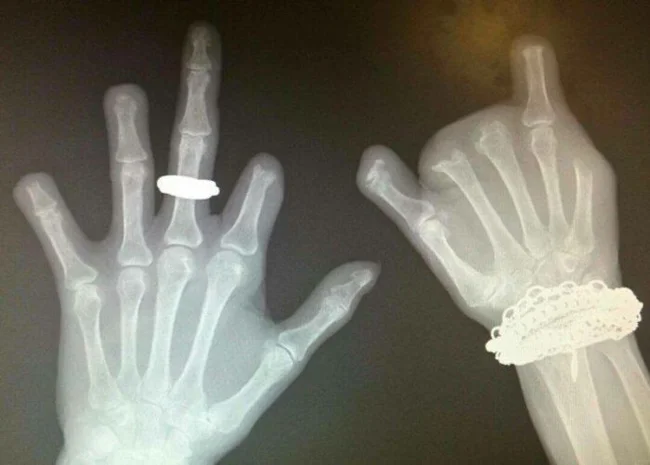

22. Рентгеновские снимки рук ребёнка и взрослого

12. Рентген пациента, который долгое время жевал и обгрызал пальцы до кости

Это привело к тяжёлым бактериальным инфекциям и многократным ампутациям.